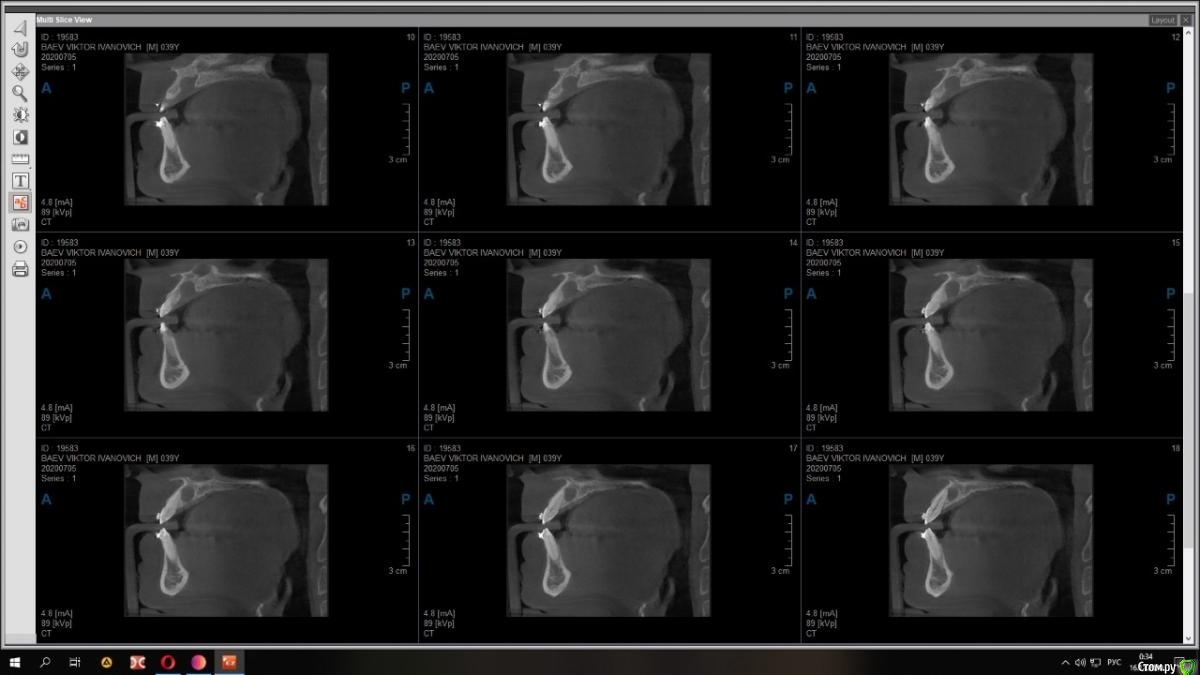

Raystom Опубликовано 18 декабря, 2020 Автор Поделиться Опубликовано 18 декабря, 2020 Срезы из других проекций Ссылка на комментарий

bilal Опубликовано 19 декабря, 2020 Поделиться Опубликовано 19 декабря, 2020 c чего вы решили что киста. как будто расширенный канал просто Ссылка на комментарий

Raystom Опубликовано 21 декабря, 2020 Автор Поделиться Опубликовано 21 декабря, 2020 c чего вы решили что киста. как будто расширенный канал просто ну не, это 80 процентов она Ссылка на комментарий